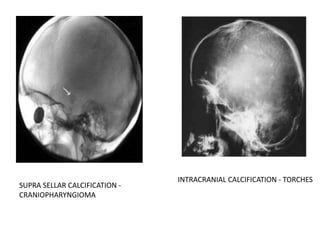

• Neoplasm – Craniopharyngioma, Astrocytoma, oligodendroglioma, pinealoma

SUPRA SELLAR CALCIFICATION -

CRANIOPHARYNGIOMA

INTRACRANIAL CALCIFICATION - TORCHES